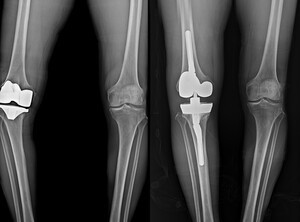

• 연세사랑병원, 무릎 인공관절 재수술 1천례 달성

연세사랑병원, 무릎 인공관절 재수술 1천례 달성

보건복지부 지정 관절전문 연세사랑병원이 무릎 인공관절 재수술 1천례를 달성했다.연세사랑병원은 최근 10년 동안 833례의 재치환술을 시행해 국내에서 손꼽히는 재수술 경험을 보유한 의료기관으로 확인됐다.무릎 인공관절의 내구성은 현재 평균 20년 정도로 보고된다. 과거 10~15년 수준이던 수명이 꾸준히 향상됐다. 이는 제3세대 인공관절 디자인의 발전 ▲ 네비게이션 수술 ▲ 로봇 수술 ▲ AI 기반 3D 시뮬레이션 ▲ 맞춤형 수술도구 등 다양한 기술 도입으로 수술 정확도가 높아진 데 따른 결과다.그러나 평균 수명 증가에 따른 인공관절

• 연세사랑병원, 인공관절 재수술센터 개설과 고난도 협진 치료 착수

연세사랑병원, 인공관절 재수술센터 개설과 고난도 협진 치료 착수

보건복지부 지정 관절전문 연세사랑병원이 인공관절 재수술 환자 증가에 대응하기 위해 '인공관절 재수술센터'를 개설했다. 이 센터는 무릎 인공관절 재치환술과 수술 후 지속되는 통증 환자 치료에 전문적인 진료체계를 구축했다.무릎 인공관절 수술은 2000년대 초반 평균 10~15년 내외의 수명을 보였으나, 최근 의료기술 발전으로 20년 이상 사용 가능하도록 내구성이 향상됐다. 그러나 수술 정확도, 개인별 관리 상태, 활동량 등 다양한 요인에 따라 인공관절이 마모 및 이완돼 재수술이 필요한 사례가 꾸준히 보고되고 있다. 국내외 연구에 따르면